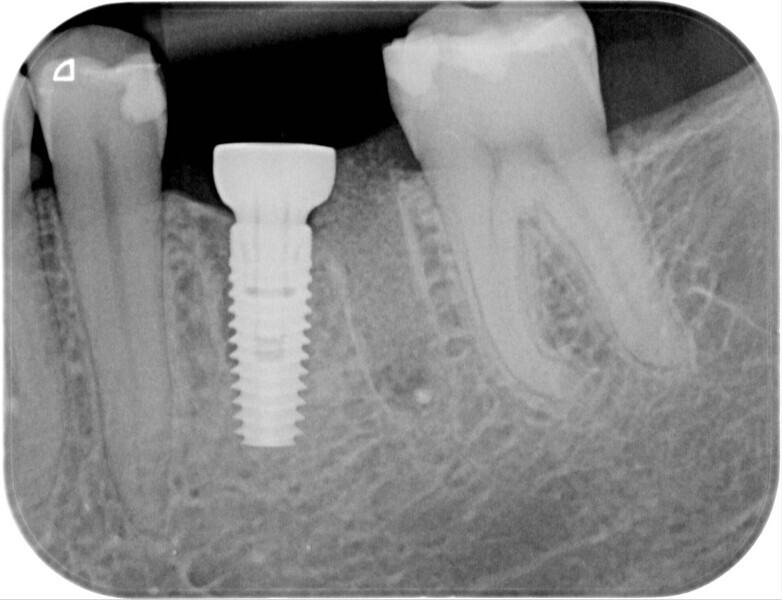

Immediately after implant placement (Fig. 5), the abutment position was registered with an intra-oral scan using Primescan (Dentsply Sirona; Fig. 6). At the end of the surgical procedure, the socket was grafted with Symbios (Dentsply Sirona) and a healing abutment was seated (Fig. 7). Radiographic evaluation was performed on the same day (Fig. 8). On basis of an intra-oral scan, an Atlantis abutment and Atlantis provisional crown were designed and fabricated with an Atlantis IO FLO (Fig. 9).

During the healing period, the final crown was manufactured based on the Atlantis Core File. Eight weeks after implant placement, the soft tissue had healed well (Figs. 15 & 16) and was ready for the final zirconia crown (Fig. 17). Radiographic evaluation with the final restoration confirmed the successful outcome of the treatment (Fig. 18).